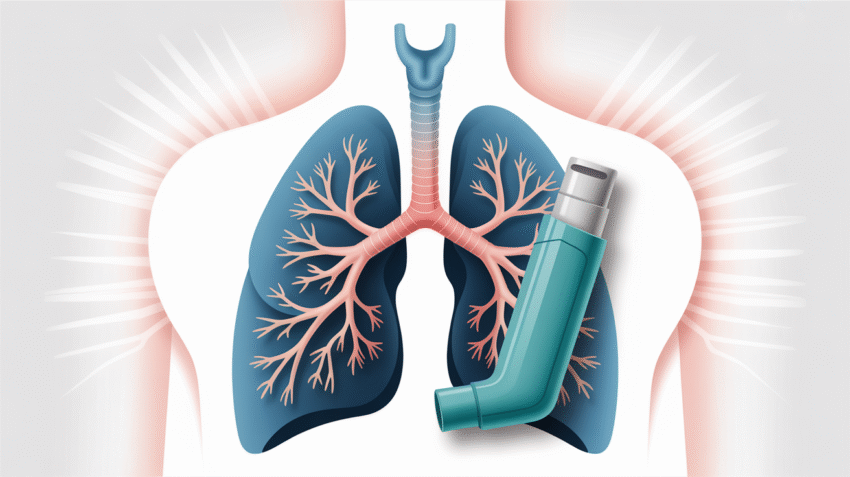

Gejala asma adalah kumpulan tanda-tanda klinis yang muncul akibat peradangan dan penyempitan saluran pernapasan, ditandai dengan sesak napas, mengi, batuk, dan rasa sesak di dada yang dapat bervariasi intensitasnya dari ringan hingga mengancam jiwa.

Mengi (Wheezing)

Mengi adalah suara “ngik-ngik” atau siulan yang terdengar saat bernapas, terutama saat menghembuskan napas. Suara ini terjadi karena udara dipaksa melalui saluran napas yang menyempit. Perlu diketahui bahwa tidak semua penderita asma mengalami mengi, dan tidak semua mengi berarti asma.

Tes Fungsi Paru

Beberapa tes yang umum dilakukan untuk mendiagnosis asma:

- Spirometri: mengukur volume dan kecepatan udara yang dihembuskan

- Tes provokasi bronkus: mengukur respons saluran napas terhadap pemicu

- Pengukuran arus puncak ekspirasi (peak flow)

- Tes nitric oxide ekshalasi: mengukur tingkat peradangan

Obat Pengendali Jangka Panjang

Obat-obatan ini digunakan setiap hari untuk mencegah munculnya gejala:

- Kortikosteroid inhalasi untuk mengurangi peradangan

- Long-acting beta agonists (LABA) untuk melebarkan saluran napas